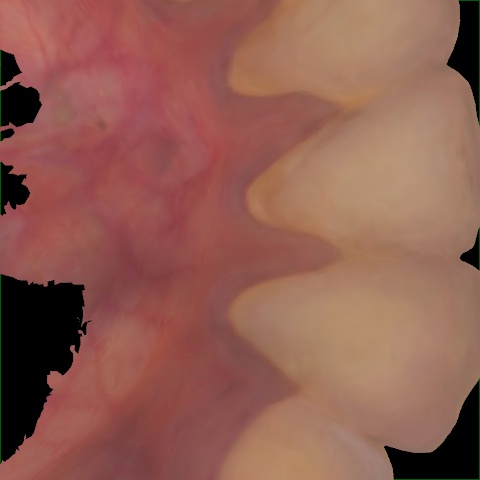

Image 239 / 313

NHD25470

Annotated as "Good"

Original Image Rendering Image